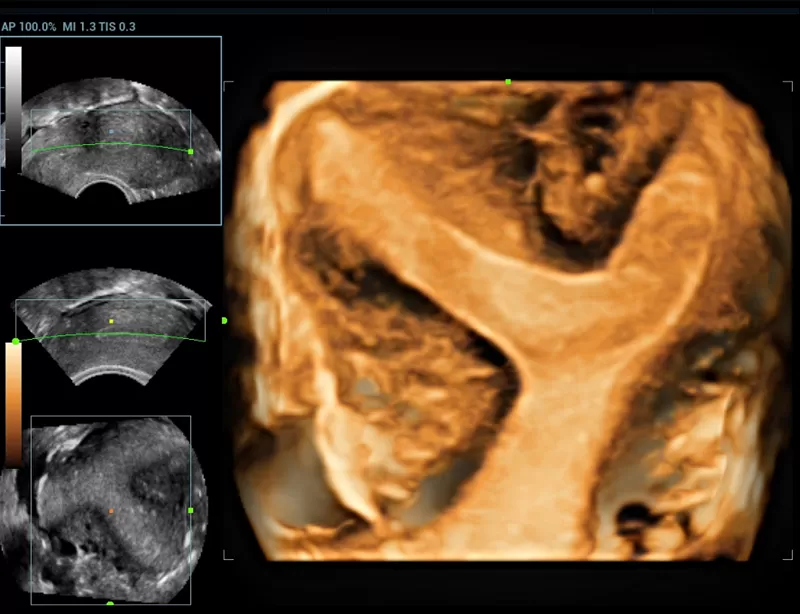

The Resona series, stands out not only for its cutting edge imaging technology but also for its flexible analysis tools offering high display quality and increased diagnostic precision.

The innovative technologies:

- New iLive with Hyaline